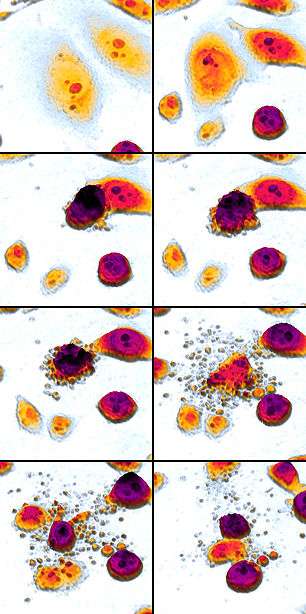

An etoposide-treated DU145 prostate cancer cell exploding into a cascade of apoptotic bodies. The sub images were extracted from a 61-hour time-lapse microscopy video, created using quantitative phase-contrast microscopy. The optical thickness is color-coded. With increasing thickness, color changes from gray to yellow, red, purple and finally black.[1] See the video at The Cell: An Image Library | |

Apoptosis (from Ancient Greek ἀπόπτωσις "falling off") is a process of programmed cell death that occurs in multicellular organisms.[2] Biochemical events lead to characteristic cell changes (morphology) and death. These changes include blebbing, cell shrinkage, nuclear fragmentation, chromatin condensation, chromosomal DNA fragmentation, and global mRNA decay. Between 50 and 70 billion cells die each day due to apoptosis in the average human adult.[lower-alpha 1] For an average child between the ages of 8 and 14, approximately 20 billion to 30 billion cells die a day.[4]

In order to perform analysis of apoptotic versus necrotic (necroptotic) cells, one can do analysis of morphology by time-lapse microscopy, flow fluorocytometry, and transmission electron microscopy. There are also various biochemical techniques for analysis of cell surface markers (phosphatidylserine exposure versus cell permeability by flow fluorocytometry), cellular markers such as DNA fragmentation[53] (flow fluorocytometry), caspase activation, Bid cleavage, and cytochrome c release (Western blotting). It is important to know how primary and secondary necrotic cells can be distinguished by analysis of supernatant for caspases, HMGB1, and release of cytokeratin 18. However, no distinct surface or biochemical markers of necrotic cell death have been identified yet, and only negative markers are available. These include absence of apoptotic markers (caspase activation, cytochrome c release, and oligonucleosomal DNA fragmentation) and differential kinetics of cell death markers (phosphatidylserine exposure and cell membrane permeabilization). A selection of techniques that can be used to distinguish apoptosis from necroptotic cells could be found in these references.[54][55][56]